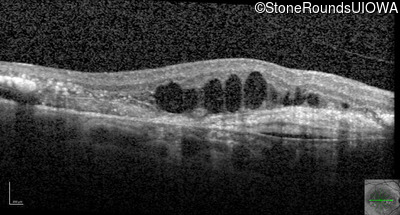

Optical Coherence Tomography - Right - 20/200 +1

Exemplar / OCT Stack

Infrared Fundus Photograph - Right - 20/200 +1